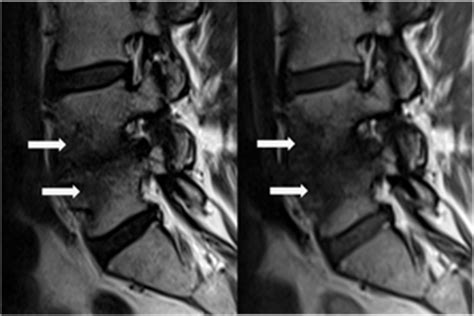

Diagnosing Modic Type 1 Endplate Changes requires high-quality MRI imaging. Because these changes involve fluid and bone marrow, standard X-rays or CT scans are generally insufficient to see the soft-tissue-like inflammation. An MRI provides the necessary detail to differentiate between the active inflammatory state of Type 1 and the more stable, chronic states of Types 2 and 3.

Physicians will typically look for a "bright" signal on T2-weighted images and a "dark" signal on T1-weighted images at the level of the disc space. While these findings are objective, it is essential for clinicians to correlate these images with the patient's physical symptoms. In some cases, Modic changes can be found in asymptomatic individuals, so a comprehensive clinical exam is always required.

One of the unique aspects of Modic Type 1 Endplate Changes is their dynamic nature. Unlike Type 2 or Type 3, which tend to remain static, Type 1 can evolve. Over time, an inflammatory Type 1 lesion may transition into a Type 2 lesion, indicating that the acute inflammatory phase has subsided and the body has replaced the inflamed bone marrow with fat.

Patients often find that as the inflammation subsides and the tissue transitions to a Type 2 appearance, the intensity of their back pain may decrease. Regular monitoring through follow-up MRIs is sometimes used to track this healing trajectory, providing both the patient and the physician with visual evidence of clinical progress.